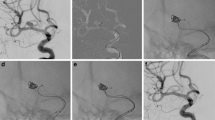

Catheterization of the aneurysm. The short (lesser) and long (greater) curves are shown in green and yellow, respectively (a). The microwire and microcatheter are advanced proximal to the aneurysm. Doing so introduces load into the system, reflected by the microcatheter pushed externally to the greater vessel curves and descent of the guide catheter (b). Load is removed from the system by gently withdrawing the microcatheter, resulting in the guide catheter returning to its previous position and the microcatheter shifting to the lesser curves. The microwire is then advanced into the aneurysm (c). The wire is pinned, and the mirocatheter is advanced over the wire into the aneurysm, just beyond the neck. Note that load is again introduced into the system with this maneuver (d). With the catheter in the desired position, a small amount of load is once again removed (e). Note that the microcatheter tip position does not change but instead the shape of the exposed microcatheter. The wire is then gently removed from the microcatheter (f). A framing coil is then deployed into the aneurysm (g). Oftentimes this may require forward load on the microcatheter if the coil pushes the microcatheter proximally. Coiling is then completed (h)

Under road map guidance using the working view, the microcatheter and microwire are then carefully and slowly navigated to the aneurysm (Fig. 10.2). This is performed by leading with the microwire and gently spinning the wire so that it steers in the direction of interest. Control of the wire is enhanced by having proximal support from the microcatheter, so after the wire is advanced a reasonable distance without the catheter, it is helpful to “pin” the wire by holding it in place and then advancing the microcatheter to a point near the wire tip. The wire is then slowly steered and advanced forward. This process is repeated until the microcatheter and wire are near the aneurysm neck. Attention should be paid toward inadvertent advancement of the wire into tiny perforating branches so that this can be immediately recognized and/or avoided.

Catheterization of the aneurysm is then performed by slowly and carefully advancing the microwire into the aneurysm. Contact with the aneurysm dome wall by the microwire is not necessary or recommended. Next, with appreciation of the load within the system, the microcatheter is slowly advanced over the microwire while pinning the microwire. Often, even with the microwire pinned, the microwire will continue to demonstrate subtle movements while the microcatheter is being advanced. This may necessitate slight withdrawal or advancement of the wire to hold a stable position. This “push and pull” is important for keeping a steady wire position, particularly when the system is under load. If one-to-one movement is absent with microcatheter advancement, extreme care is necessary when supplying forward force on the microcatheter. Often times removing load from the system before delicate microcatheter work will improve control. The microcatheter should then be advanced into the aneurysm over the wire, away from the aneurysm wall. If the catheter is too deep in the aneurysm and in contact with or near the aneurysm dome wall, there is a risk of perforation from the leading segment of the coil when it is deployed. In most cases, position of the microcatheter at, or just beyond, the neck is usually preferred. Once a satisfactory position is reached, the microcatheter is pulled back slightly to remove excess load from the system, which will subtly straighten the microcatheter in the proximal loops but not affect catheter tip position. Care must be taken with this step because if too much load is removed, the microcatheter tip may lose its position and fall into the parent vessel. The microwire is then removed under initial fluoroscopic visualization to ensure the catheter tip does not shift.